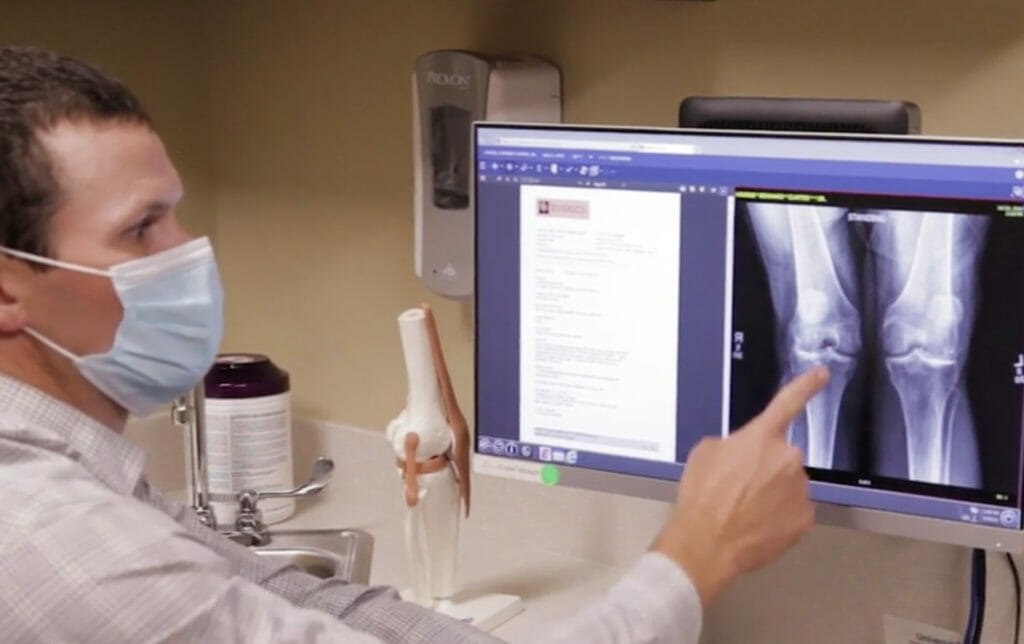

Some of their most common procedures are hip replacement, shoulder replacement and knee replacement. If you are looking for a definitive solution to your arthritis, they have procedures that can resolve it.